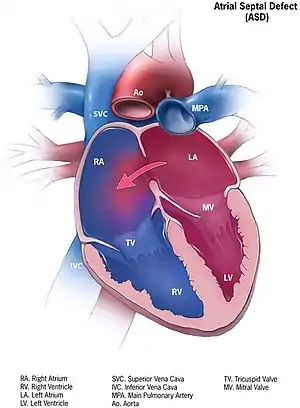

| Illustration of an atrial septal defect. | |

Atrial septal defect (ASD) is a congenital heart defect in which blood flows between the atria (upper chambers) of the heart. Some flow is a normal condition both pre-birth and immediately post-birth via the foramen ovale; however, when this does not naturally close after birth it is referred to as a patent (open) foramen ovale (PFO). It is common in patients with a congenital atrial septal aneurysm (ASA).

After PFO closure the atria normally are separated by a dividing wall, the interatrial septum. If this septum is defective or absent, then oxygen-rich blood can flow directly from the left side of the heart to mix with the oxygen-poor blood in the right side of the heart; or the opposite, depending on whether the left or right atrium has the higher blood pressure.[1] In the absence of other heart defects, the left atrium has the higher pressure. This can lead to lower-than-normal oxygen levels in the arterial blood that supplies the brain, organs, and tissues. However, an ASD may not produce noticeable signs or symptoms, especially if the defect is small. Also, in terms of health risks, people who have had a cryptogenic stroke are more likely to have a PFO than the general population.[2]

A cardiac shunt is the presence of a net flow of blood through a defect, either from left to right or right to left. The amount of shunting present, if any, determines the hemodynamic significance of the ASD. A right-to-left-shunt results in venous blood entering the left side of the heart and into the arterial circulation without passing through the pulmonary circulation to be oxygenated. This may result in the clinical finding of cyanosis, the presence of bluish-colored skin, especially of the lips and under the nails.

Heart of human embryo of about 35 days Atrial septal defect with left-to-right shunt

Atrial septal defect with left-to-right shunt Illustration depicting atrial septal defect

Illustration depicting atrial septal defect